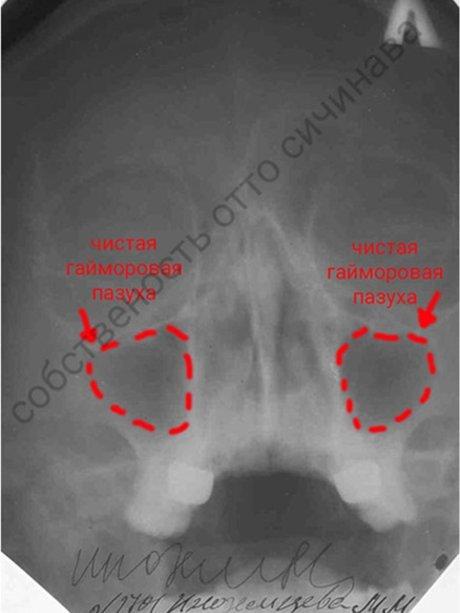

После курса лечения

На конторольной рентгенограмме пазухи воздушны (чистые).